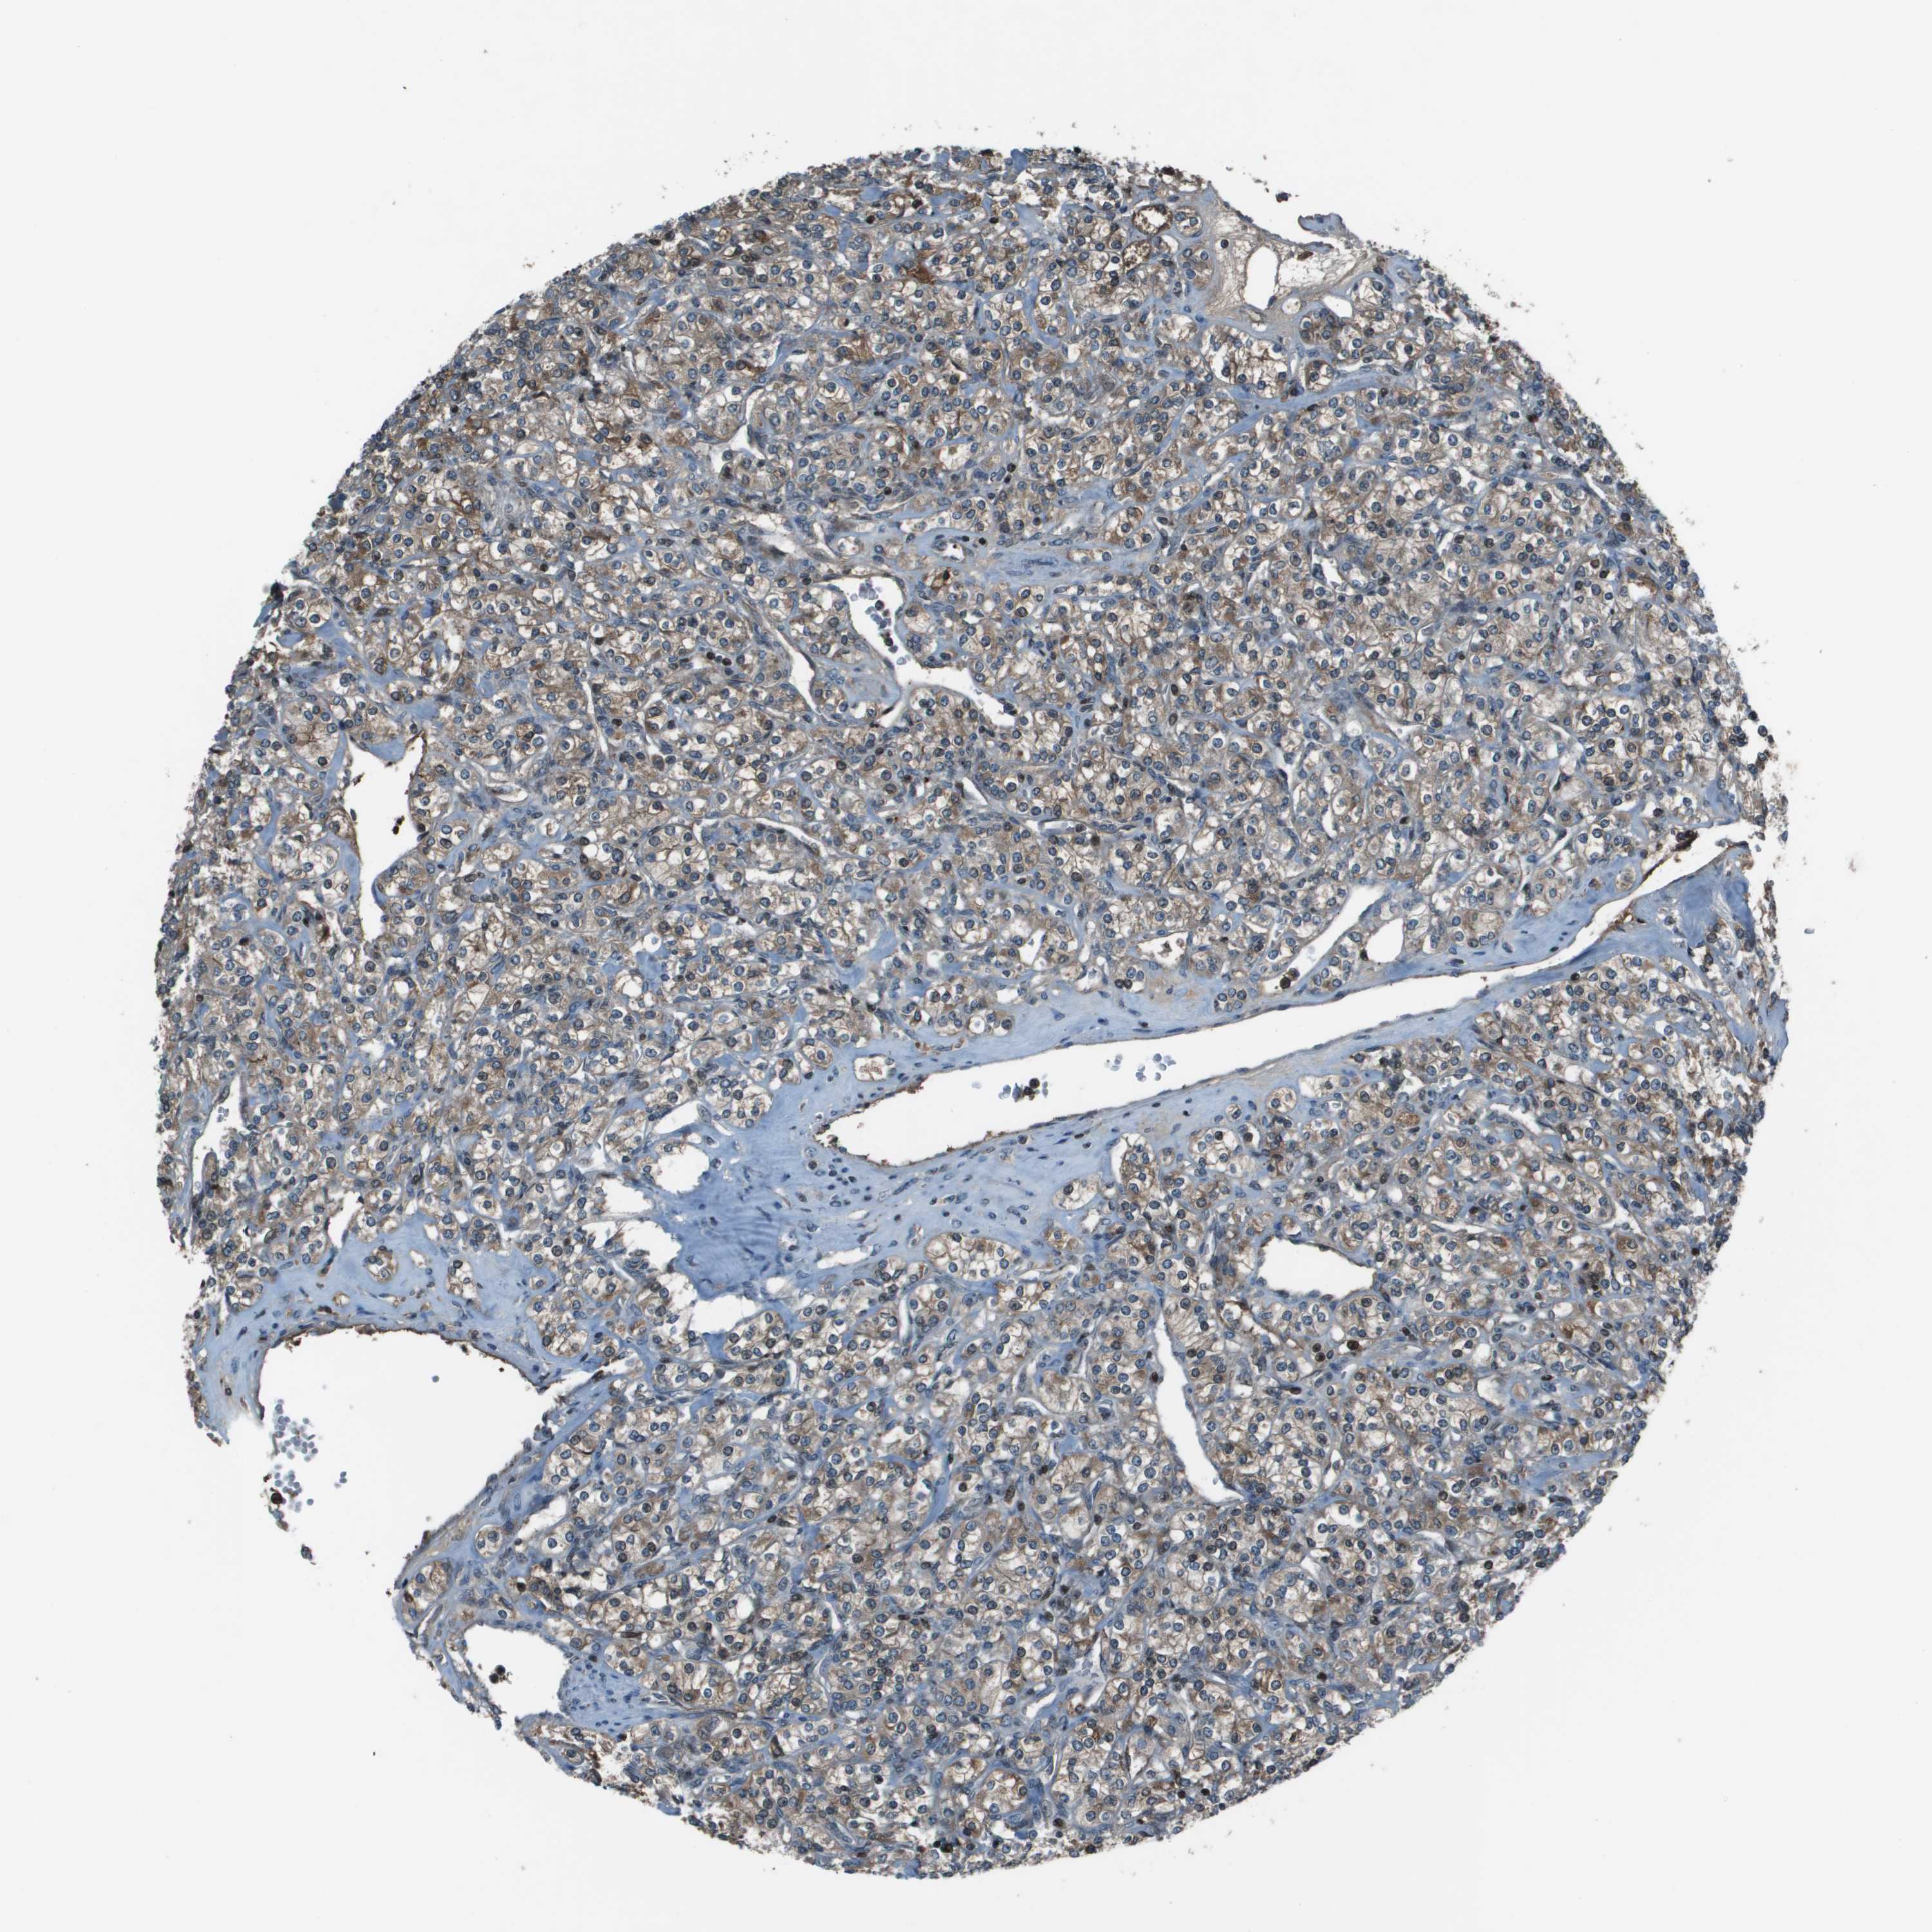

CANCER RENAL CANCER Show tissue menu

KICH TCGA KIRC TCGA KIRC VALIDATION KIRP TCGA PROTEIN RCC CPTAC PROTEIN EXPRESSION